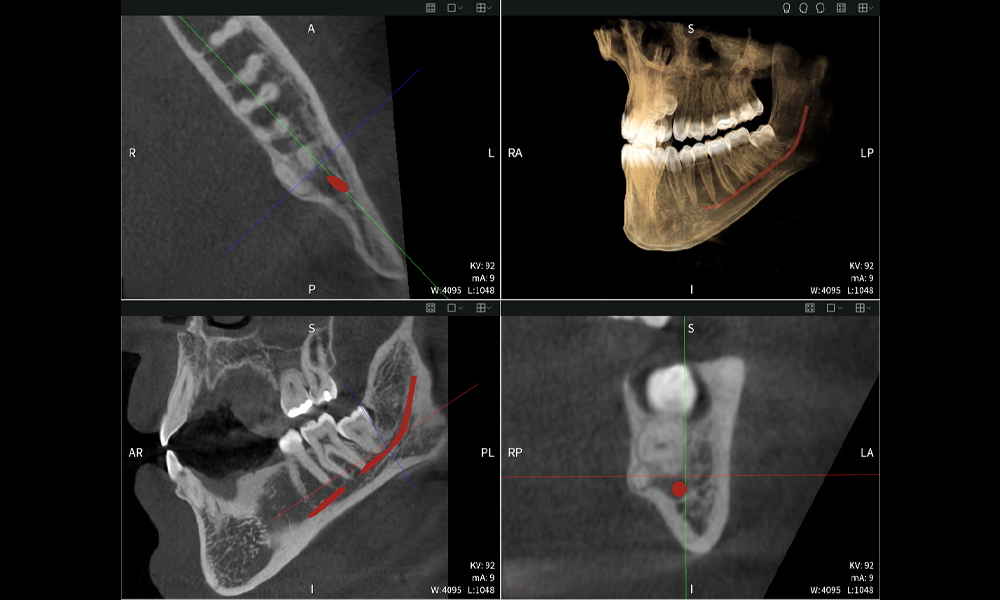

A continuación encontrarás un caso del Dr. med. dent. Oliver A. Centrella, en el cual las imágenes CBCT obtenidas con Seethrough Max proporcionaron información crucial sobre la anatomía compleja y la relación crítica entre las muelas del juicio y el nervio alveolar inferior. En este caso, existe una indicación para la extracción quirúrgica de las muelas del juicio.

Figura a: Resultados de imagen de Seethrough Max, sobre un fondo negro.

• Arriba a la izquierda: Corte axial de la mandíbula izquierda (región 38) que muestra el nervio alveolar inferior (en rojo) en proximidad a las raíces del diente 38.

• Arriba a la derecha: Reconstrucción 3D de toda la mandíbula para orientación. El nervio alveolar inferior marcado en rojo ilustra su ubicación dentro del hueso mandibular.

• Abajo a la izquierda: Vista sagital de la mandíbula (región 38), destacando la estrecha relación espacial entre las raíces y el conducto del nervio.

• Abajo a la derecha: Vista coronal de la mandíbula (región 38), crucial para evaluar la posición espacial de las raíces en relación con el nervio.